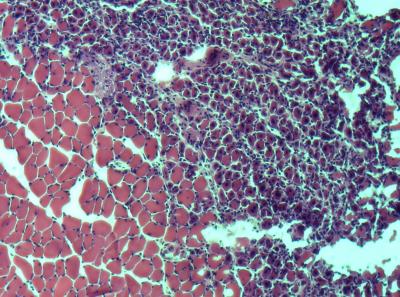

But what would happen if researchers blocked the adult stem cells in old tissues from reacting to those TGF-beta signals? The researchers put that question to the test in a living organism by comparing the muscle regeneration capacity of old, 2-year-old mice, comparable in age to a 75- to 80-year-old human, with that of 2-month-old mice, similar in age to a 20- to 25-year-old human.

For a group of the old mice, the researchers disabled the "aging pathway" that tells stem cells to stop dividing by using an established method of RNA interference that reduced levels of pSmad3. The researchers then examined the muscle of the different groups of mice one to five days after injury to compare how well the tissue repaired itself.

As expected, the researchers found that muscle tissue in the young mice easily replaced damaged cells with new, healthy cells. In contrast, the areas of damaged muscle in the control group of old mice were characterized by fibroblasts and scar tissue.

However, muscles in the old mice whose stem cell "aging pathway" had been dampened showed levels of cellular regeneration that were comparable to their much younger peers, and that were 3 to 4 times greater than those of the group of "untreated" old mice.